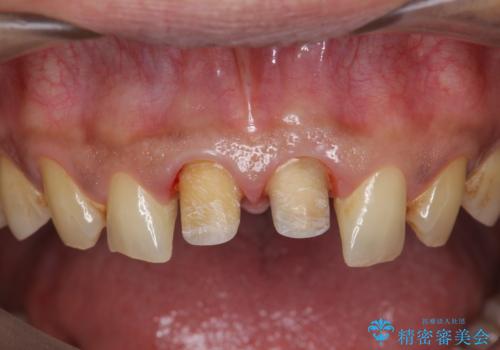

X線写真より、根尖部に透過像が認められ根管治療・ファイバーコア築盛・セラミッククラウンの作製が必要な状態です。

- 46万円(仮歯・根管治療・ファイバーコア・ジルコニアクラウン×2)費用は治療当時の料金となります